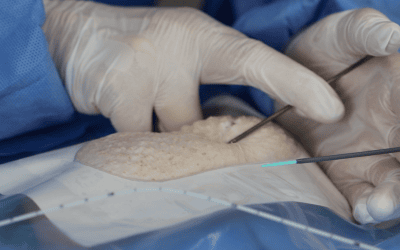

Colocación del puerto venoso

3. Acceso por la vena subclavia en adultos

Hoy en día, nuestra vía de abordaje de elección era la vena subclavia en el surco deltopectoral, lo cual permite una gran discreción para los pacientes (respeto del escote). Colocamos el 99% de nuestros puertos con este abordaje.

Se han realizado alrededor de 10.000 procedimientos en nuestro instituto desde 2007, con esta técnica y con esta técnica no hubo casos de neumotórax, punción arterial o síndrome de Pinch off.

En este caso, se crea el bolsillo de un tamaño ajustado al tamaño de la cámara ya que no se sutura a los tejidos subcutáneos. Eso permite que no se de la vuelta y evita las grandes dificultades que existen a la hora de la retirada cuando se sutura.

Se punciona la vena en el fondo del bolsillo: de esta manera el catéter tiene un recorrido más fisiológico y evitamos los posibles curvas o acodamientos que pueden crearse cuando la vena se punciona desde otro lugar.